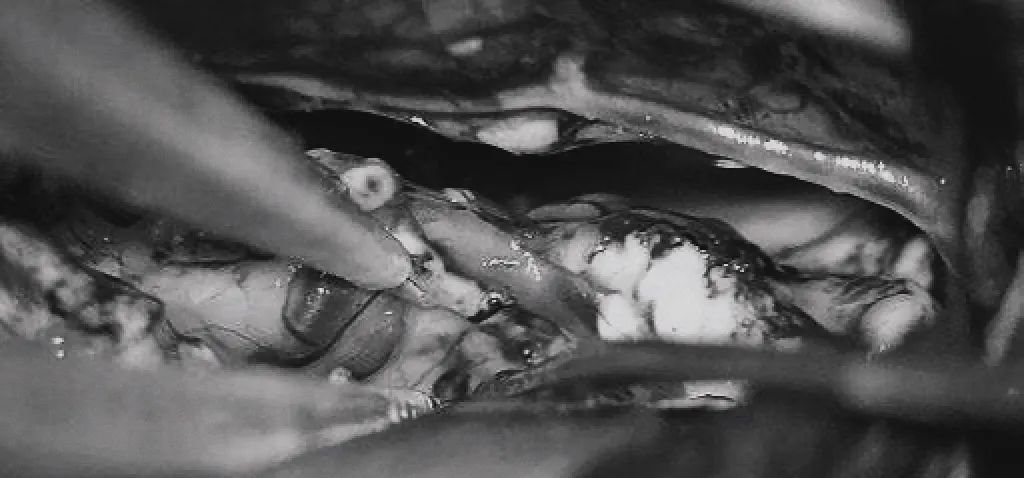

(c)双额开颅,打开纵裂(鼻朝右,中线水平位,重力牵拉右侧半球),显露胼胝体、CmaA和PcaA。(d)切开胼胝体2.5cm,显露透明隔内的AVM,大致显露ACA。